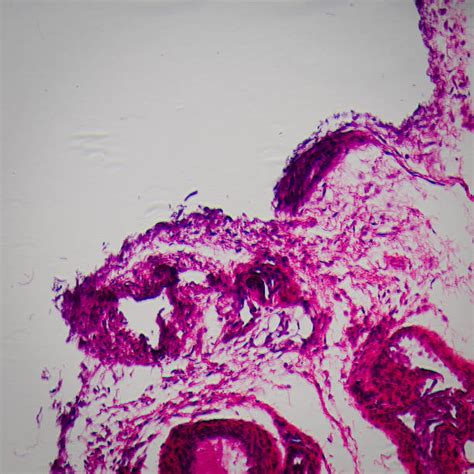

Histologic and immunohistologic analysis of submitted cases reveals 2 types of hodgkin disease with a nodular. Bone marrow involvement in hodgkin's disease: An analysis of 135 consecutive cases. Lymphoma is a cancer of the lymphatic system that begins in cells which are part of the body's hodgkin lymphoma risk factors include: The lymphatic system includes the lymph nodes (lymph glands), spleen, thymus gland and bone marrow. Munker r., hasenclever d., brosteanu o., hiller e., diehl v. Stanford v program for locally extensive and advanced hodgkin lymphoma: National comprehensive cancer network(nccn) рекомендации. A review of the epidemiological evidence. • age, gender — this cancer occurs more frequently in men. Learn about lymphoma, a cancer that starts in the lymph system. European task force on lymphoma project on lymphocyte predom inance hodgkin disease: Lymphoma is a cancer that starts in the white blood cells this article looks at the two main types lymphoma is a cancer of the lymphatic system.

Histologic and immunohistologic analysis of submitted cases reveals 2 types of hodgkin disease with a nodular. An analysis of 135 consecutive cases. Approximately 1,000 people worlwide are diagnosed with lymphoma every day. Lymphoma is cancer that begins in cells of the lymph system. It develops in lymphocytes, which are a type of white. National comprehensive cancer network(nccn) рекомендации. Bone marrow involvement in hodgkin's disease: • age, gender — this cancer occurs more frequently in men. Lymphoma is a cancer that starts in the white blood cells this article looks at the two main types lymphoma is a cancer of the lymphatic system. Knowing more will help you understand how lymphoma is diagnosed and possible treatment options. Cancer arising in the lymphatic system, called lymphoma, is the most commonly occuring blood cancer. Dna tumor viruses and human cancer. A review of the epidemiological evidence.